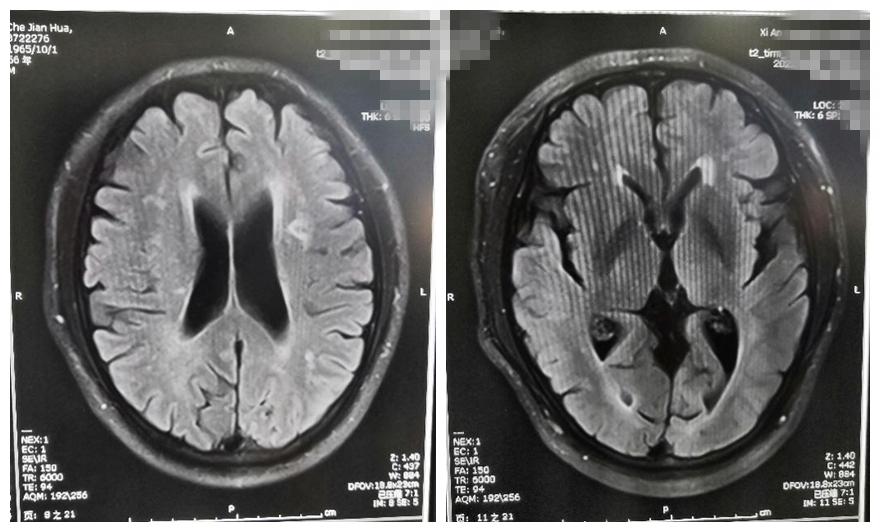

患者男性,今年56岁,平素有高血压病、糖尿病、高脂血症病史。入院前两天活动时突感头晕不适,伴右侧肢体无力,不能站立行走。休息后肢体无力症状好转,仍有头晕不适。于是到医院神经外科门诊就诊,别小华主任认真检查过患者后考虑短暂性脑缺血发作可能。行颅脑MRI提示“左侧基底节区陈旧性脑梗死,左侧顶枕叶急性腔隙性脑梗死”。

核磁共振检查

入院后完善相关检查,给予抗血小板聚集、调脂、控制血压血糖等治疗,患者病情逐渐稳定。住院期间查颅脑核磁灌注扫描提示“左侧大脑中动脉供血区域低灌注”。